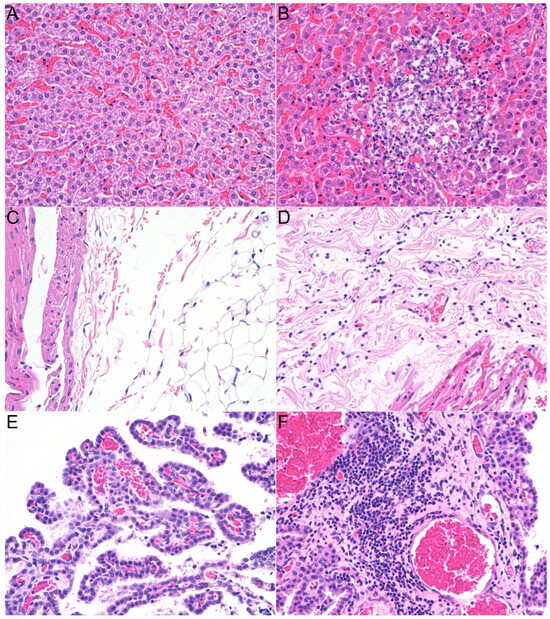

3.2. Histopathologic Lesions